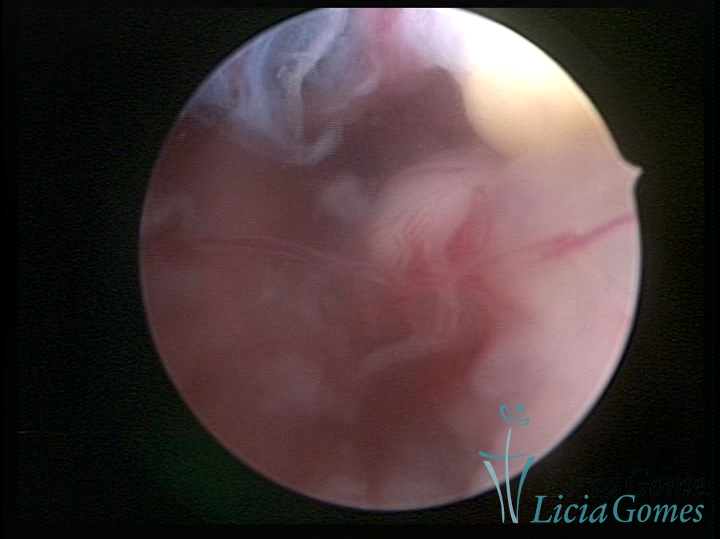

Este pode apresentar uma gama variável de aspectos macroscópicos, com aspecto pseudopolipoide; lembrando tecido cerebroide ou com reação deciduoide;a vascularização superficial é mais evidente e com vasos em formatos de saca-rolha ou espirais visualizando também a vascularização com atípias, com aumento do calibre dos vasos superficiais, pode ser encontrado também tecido em necrose, poderá haver um pequenos dendritos (papilomatoso).